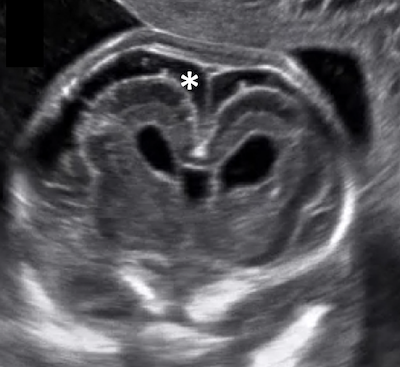

Guida al Counselling di Febbraio 2026: microcefalia

vi presentiamo la guida al counseling di Febbraio 2026 sulla microcefalia.